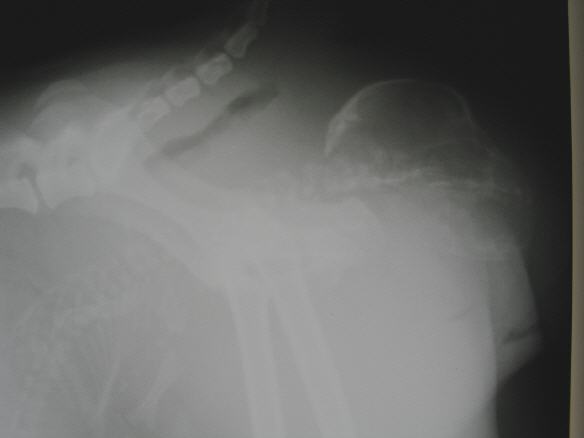

- Verlaufskontrolle der Trächtigkeit mit Ultraschall und Röntgen